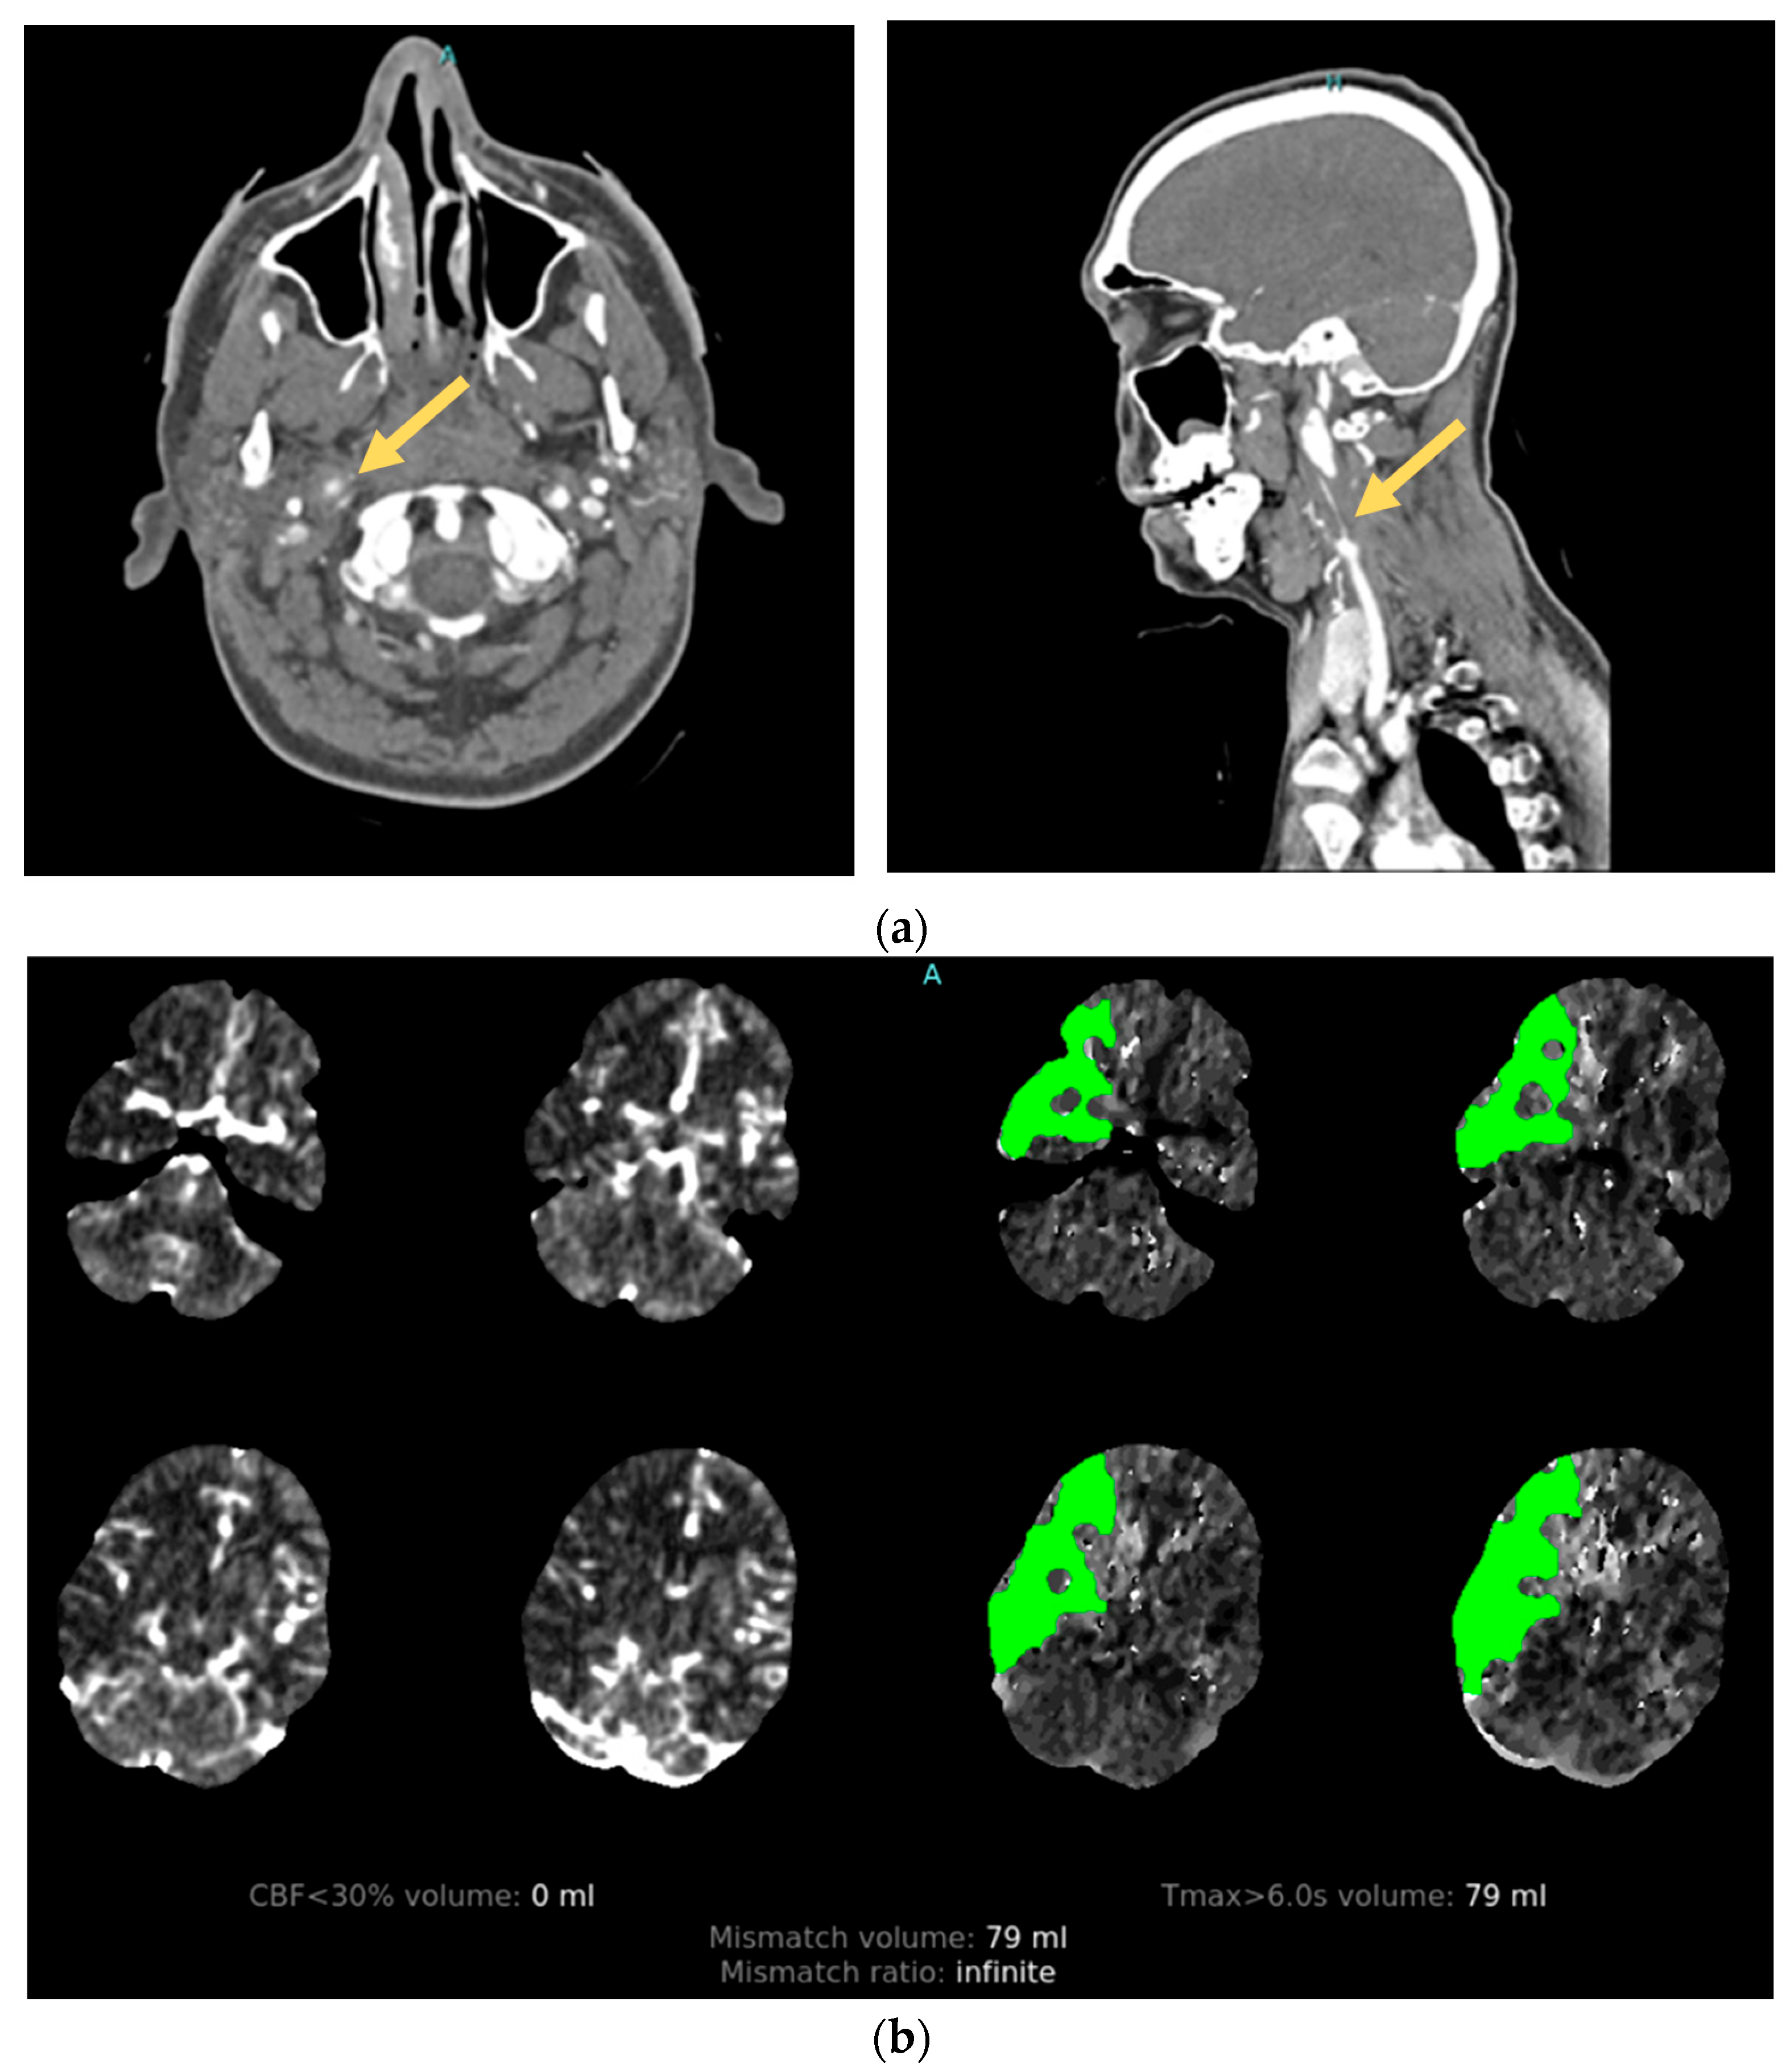

2.3. Cervical Artery Dissection

2.4. Post-Traumatic Vasospasm

3.3. Vessel Imaging

3.3.1. Angiography

3.3.2. MR Vessel Wall Imaging: An Emerging Diagnostic Tool